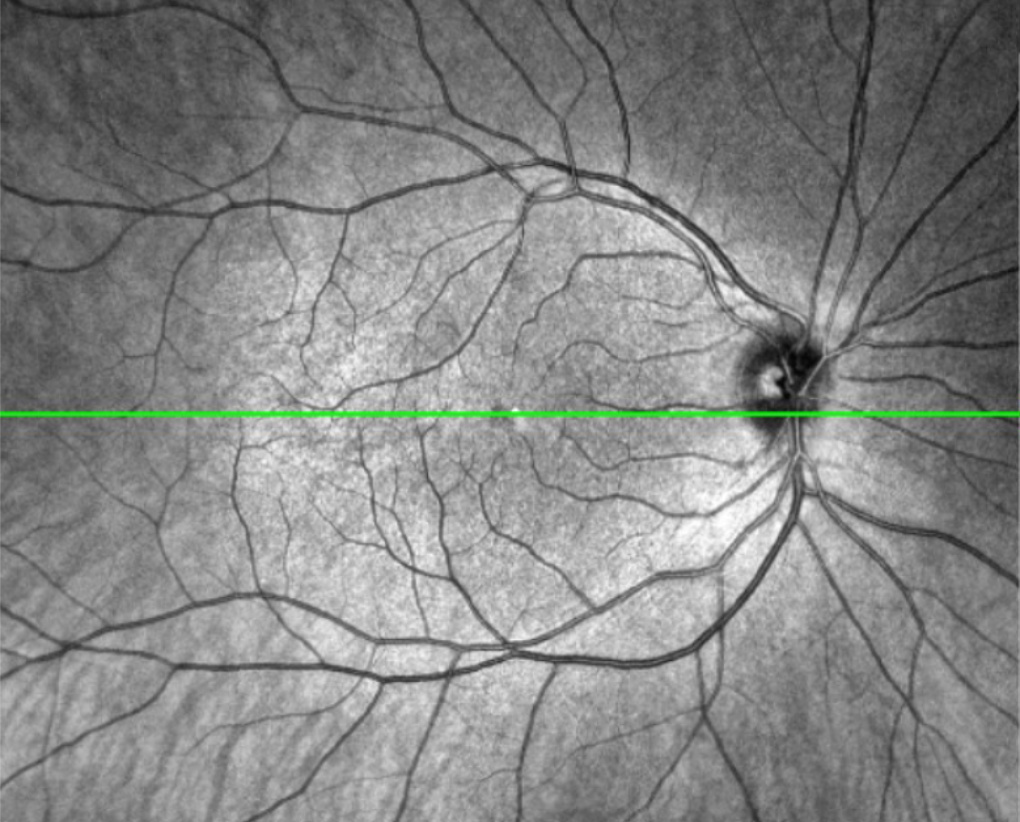

Optischer Kohärenztomographie (OCT) ist eine Bildgebungstechnologie,…

…welche zur Diagnose und Überwachung verschiedener Augenerkrankungen eingesetzt wird. Diese nicht-invasive Methode ermöglicht eine detaillierte Darstellung der Gewebestrukturen im Auge, insbesondere der Netzhautschichten.

Bei einer OCT wird ein spezieller Scanner verwendet, der mithilfe von Lichtwellen die Netzhaut und andere Augenstrukturen in hoher Auflösung abbilden kann. Das Licht wird in das Auge gesendet, wo es von den verschiedenen Gewebeschichten reflektiert wird. Die reflektierten Lichtwellen werden dann vom Scanner erfasst und in ein digitales 3D-Bild (Tomografie) umgewandelt. Das akustische Pendant dazu ist die Sonographie.

Die Optische Kohärenztomographie (OCT) wird zur Diagnose und Überwachung einer Vielzahl von Augenerkrankungen eingesetzt, darunter:

- Netzhauterkrankungen: Die OCT kann Veränderungen in den verschiedenen Schichten der Netzhaut identifizieren, was bei der Diagnose von Erkrankungen wie Makuladegeneration und diabetischer Retinopathie hilfreich ist.

- Grüner Star: Durch die Beurteilung des Zustands des Sehnervs und der retinalen Nervenfaserschicht kann die OCT helfen, das Glaukom frühzeitig zu erkennen und den Verlauf der Erkrankung zu überwachen.